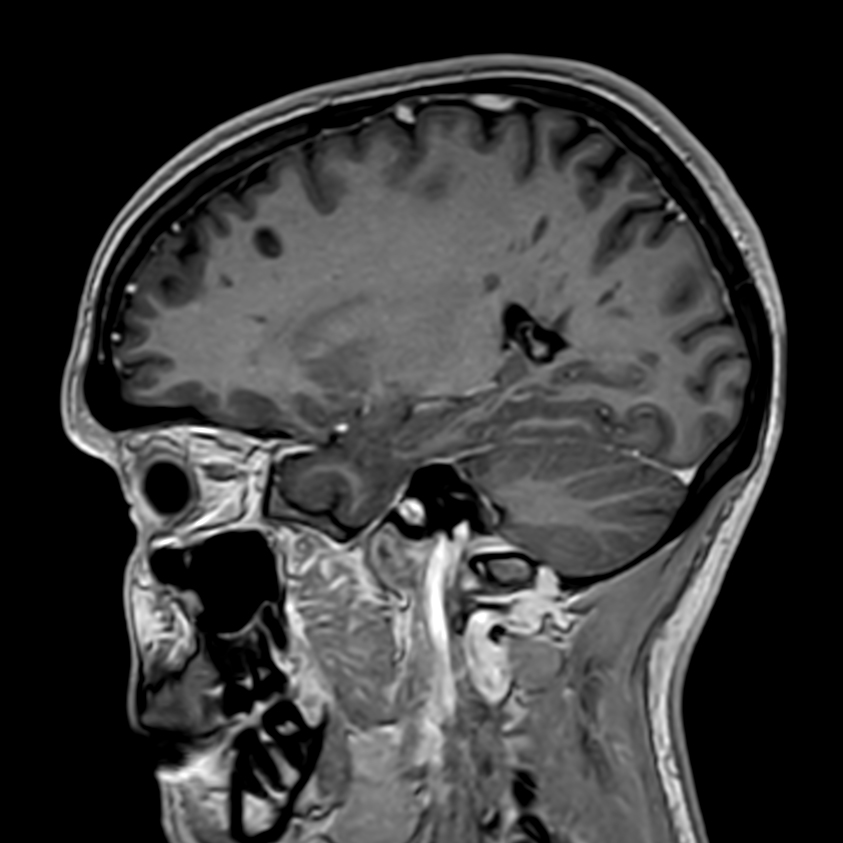

Patient with multiple brain lesions. ExamCard includes Compressed SENSE to shorten the exam time, 3D scans to acquire high resolution data in multiple directions in only one single scan and 4D-TRAK for dynamic contrast-enhanced MR Angiography enabling high spatial and temporal resolution simultaneously.

3D T1w FFE with gado (Reformat) Compressed SENSE